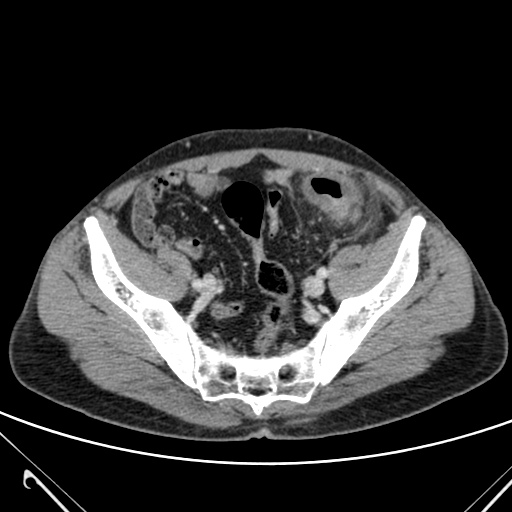

Se completa el estudio con TC de abdomen con contraste i.v.

TC ABDOMEN: Se confirman los hallazgos vistos en ecografía. Se aprecia un engrosamiento mural > 4mm de un segmento aproximado de 5.5 cm de longitud con infiltración de la grasa adyacente y sin visualizar colecciones ni gas extraluminal, hallazgos compatibles con diverticulitis aguda no complicada.

CONCLUSIÓN: Diverticulitis aguda no complicada. HINCHEY grado 0